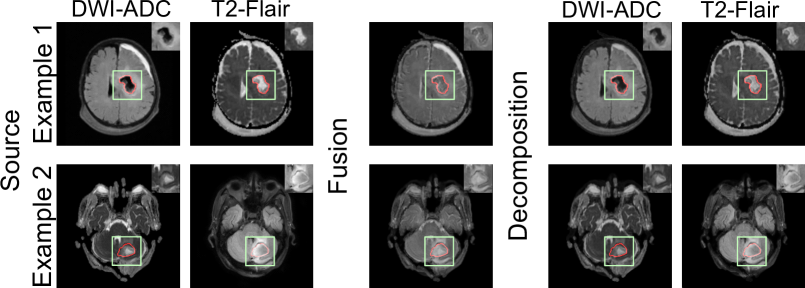

Refer to caption

Figure 5: The results from the FusionINN model on closed-source and clinically acquired post-operative image pairs. Clinicians annotated tumor boundaries (highlighted in red), and we display tumor features within green boxes on each image.

3.0.5 Clinical Translation:

Fig. 5 illustrates image pairs from DWI-ADC and T2-Flair modalities, depicting post-operative tumor regions of two patients following brain surgery. In this clinical study, medical practitioners sought fused and decomposed images to evaluate the model’s efficacy in aiding prognosis. Specifically, the model was expected to delineate features in T2-Flair indicative of the tumor’s anatomical boundary while preserving high- and low-intensity DWI-ADC features related to residual necrotic and enhancing tumor tissues, respectively. The results show that FusionINN preserves the salient features from both modalities in its decomposed images and effectively combines source features into the fused image. These findings should potentially assist clinicians in making better diagnostic decisions.